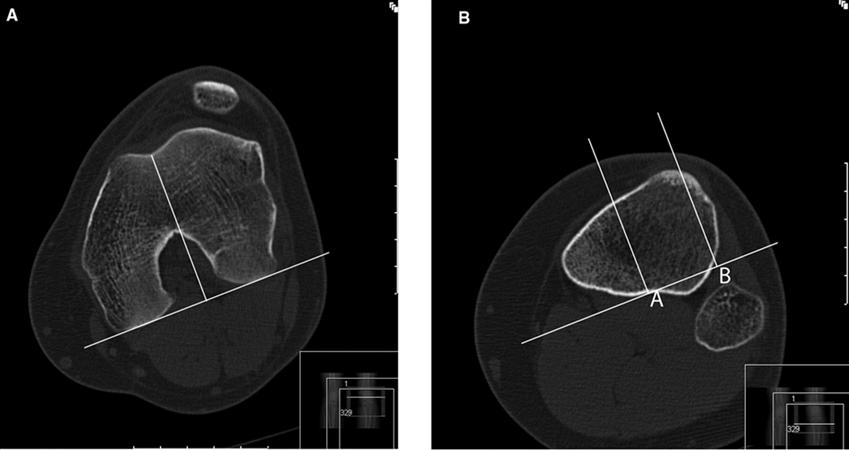

Evidence of lateral patellar compression syndrome (LPCS) at MRI

Evidence of lateral patellar compression syndrome (lpcs) at mriLateral patellar compression syndrome Lateral syndrome compression patellar specialists orthopaedicPatellar compression.